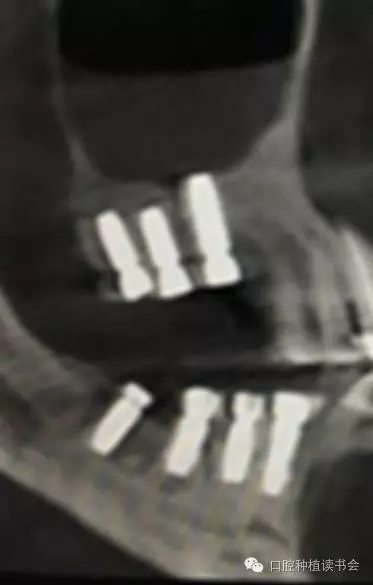

2、經(jīng)側(cè)壁開窗分離粘膜抬高竇底的方法稱為外提升(Lateral Window Technique)。早期由Philip?Boyne提出,后來上頜竇側(cè)壁開窗在粘膜和竇底之間進行骨增量的術(shù)式逐步應(yīng)用開來。側(cè)壁開窗后是否同期植入種植體,根據(jù)RBH,種植體穩(wěn)定性的預判而決定??偟膩碚f,上頜竇外提升術(shù)的成功率86%~100%(Jensen,2009)。根據(jù)CBCT圖像,不但可以提供術(shù)前的種植計劃指導,而且上頜竇外提升術(shù)后的效果,尤其是檢查種植體腭側(cè)是否有植骨不全,都會一目了然。(圖10-12)